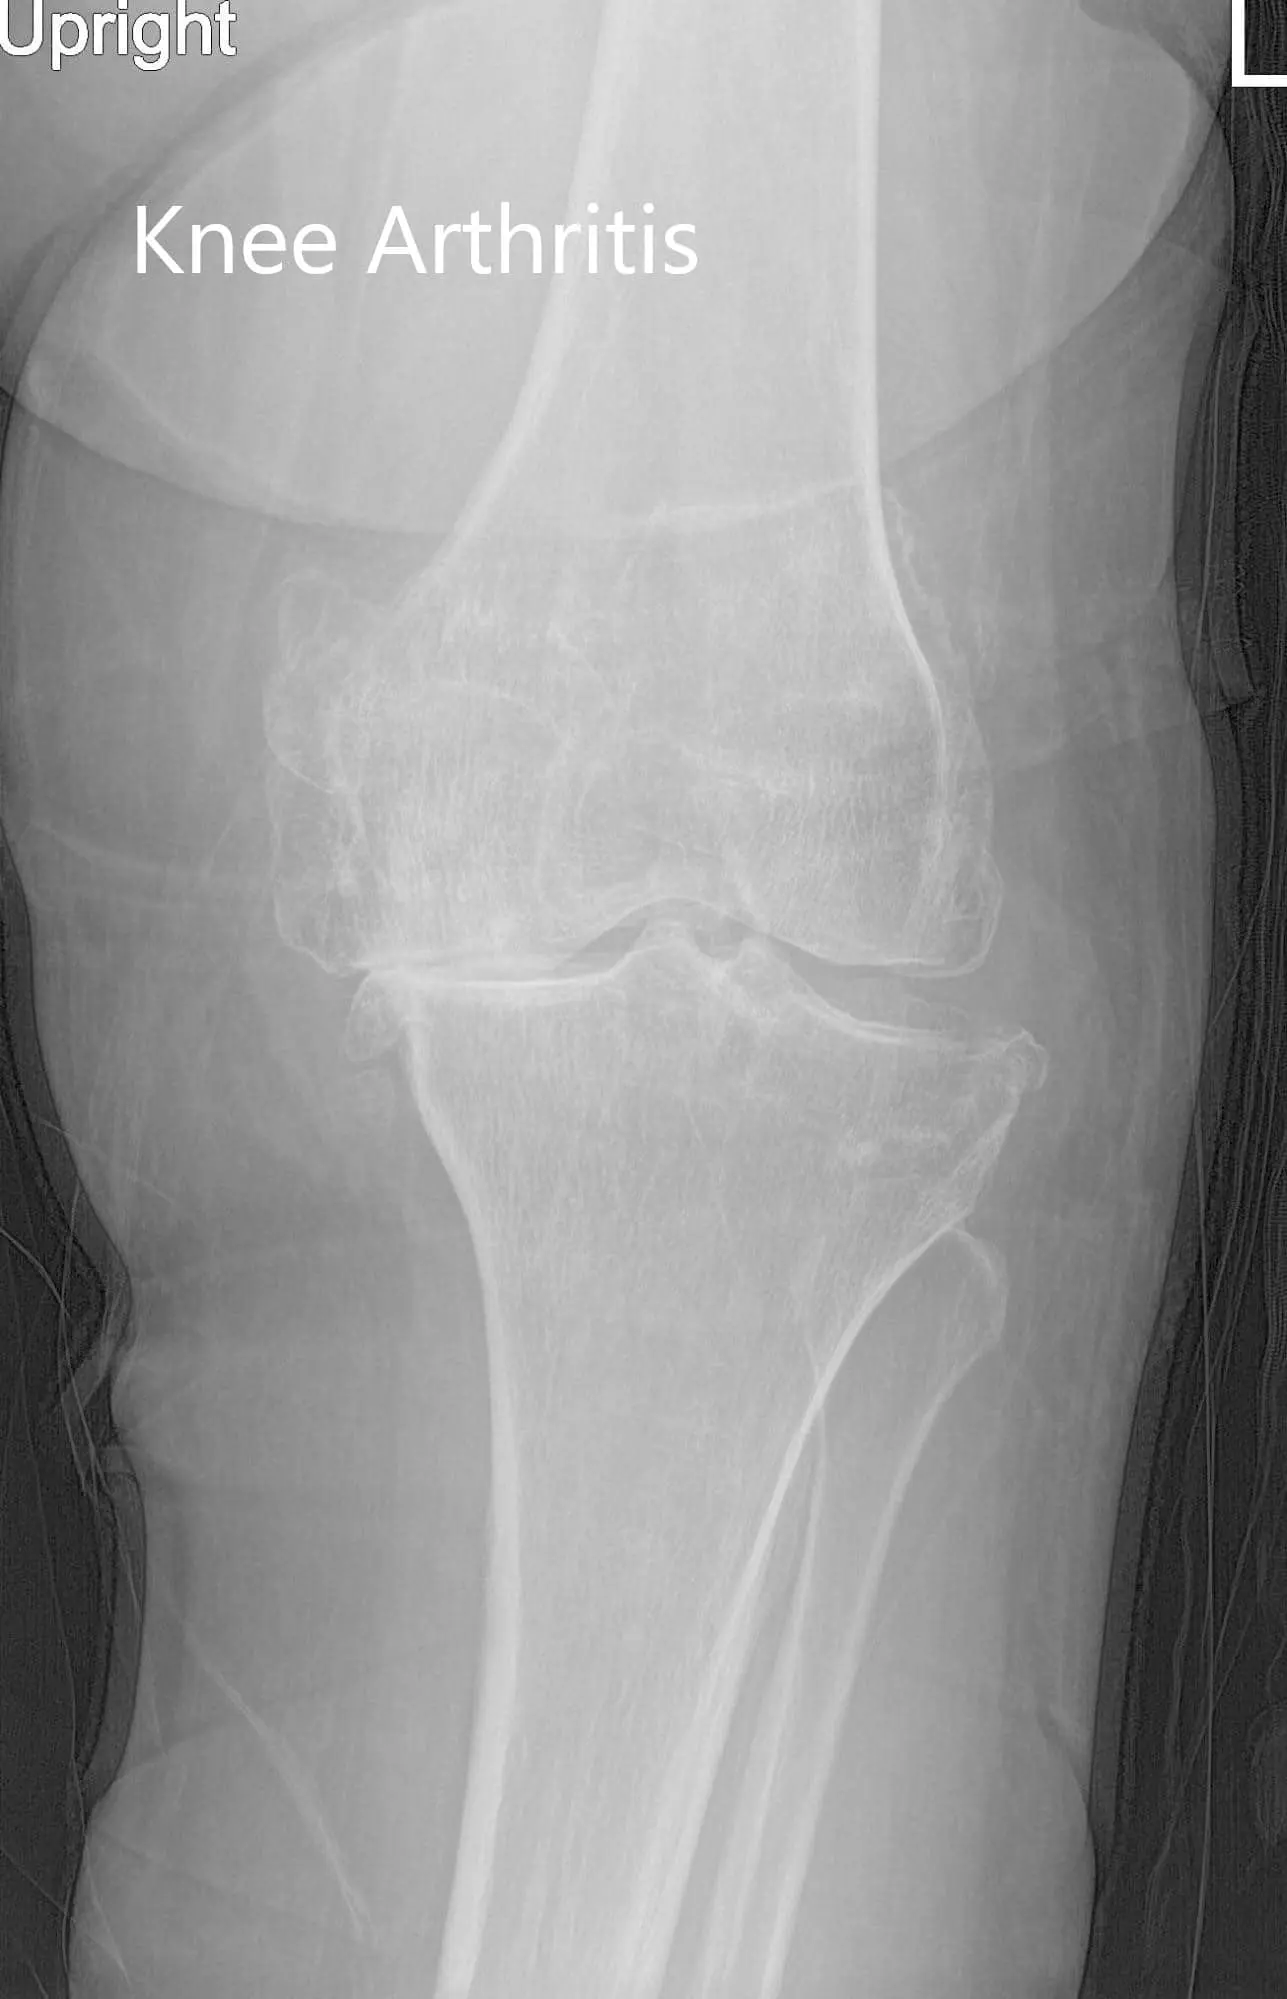

Preoperative X-ray of the left knee showing AP and lateral views